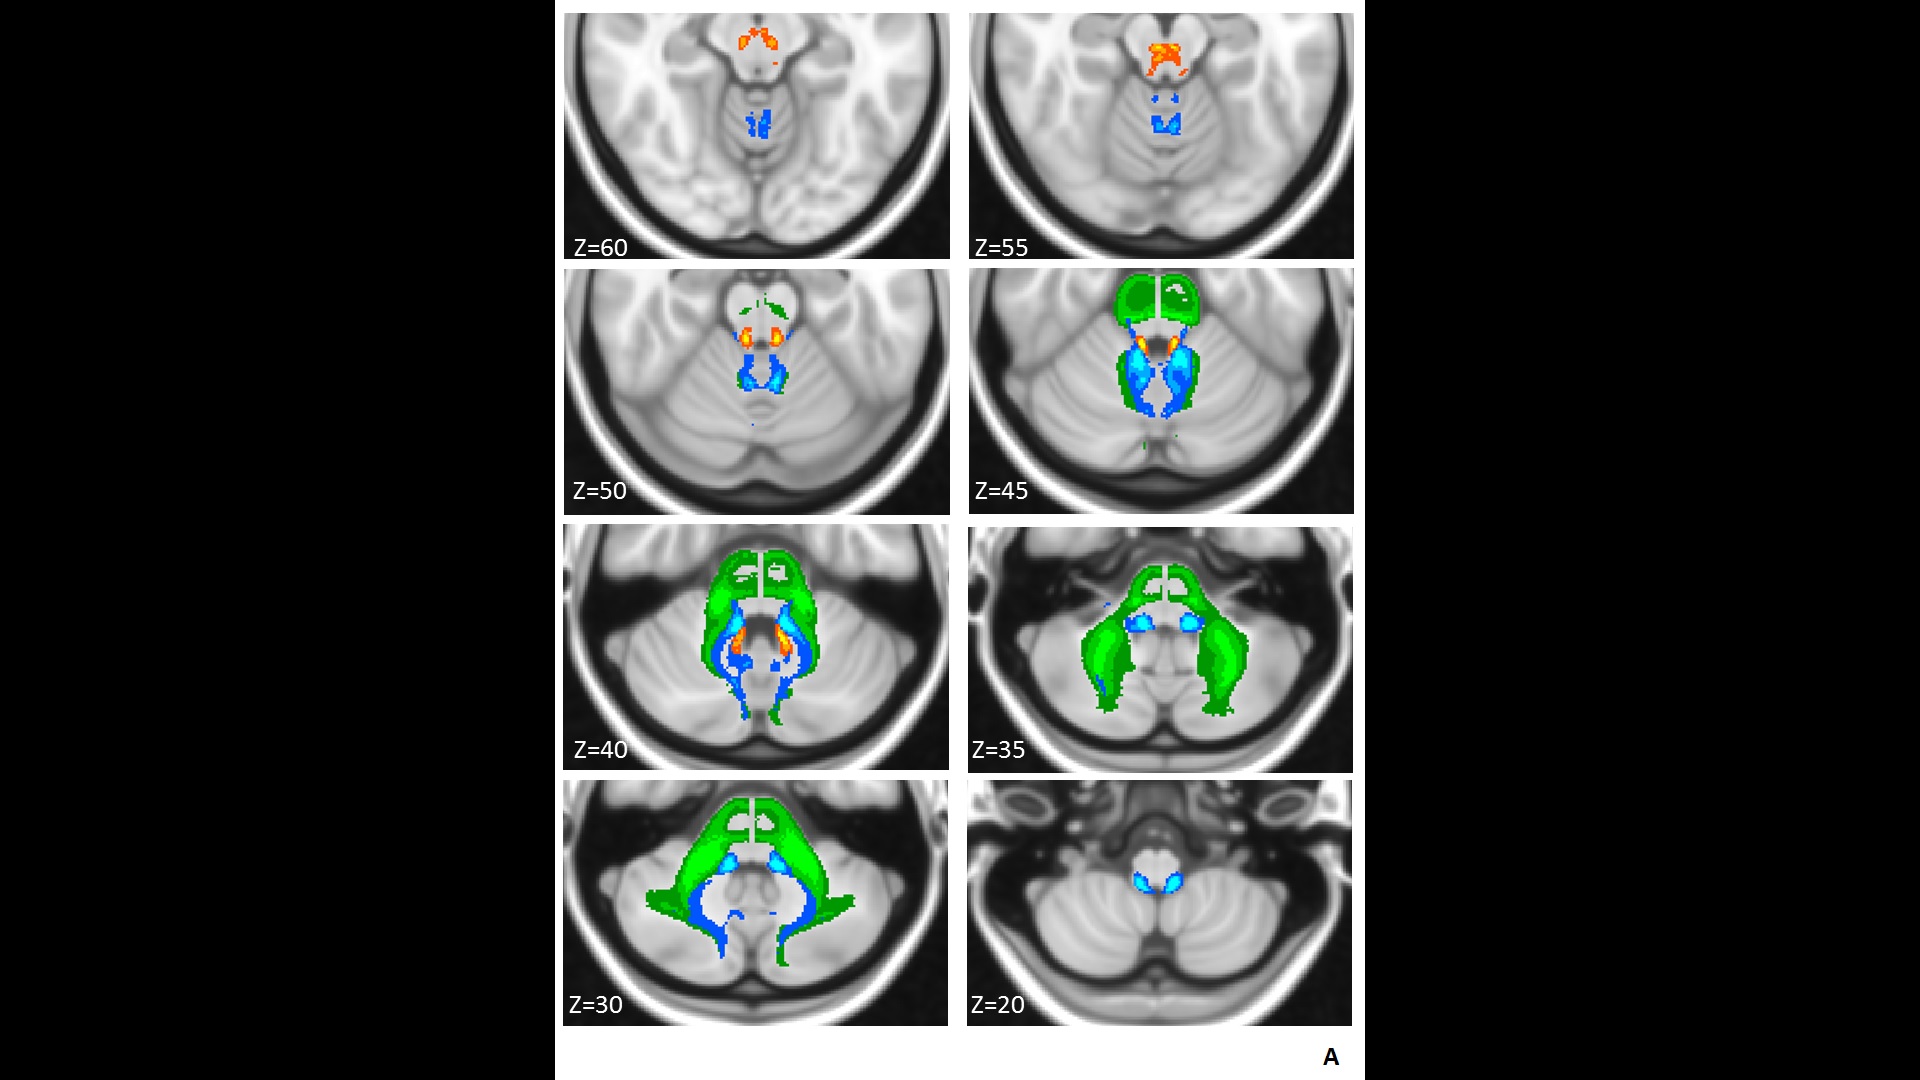

Cerebellar White Matter Atlas Images

2 Images available.

Description:parcellations at of 10, 50 and 90 percent probability